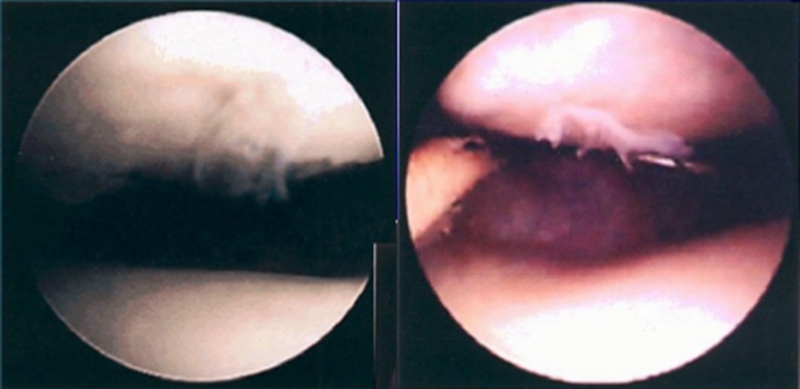

关节镜下可将髌骨软化分为5级

0级:正常关节软骨

Ⅰ级:关节软骨失去珍珠样外观而变得较暗淡,局部软化,肿胀区或纤毛化区的直径<0.5cm。

Ⅱ级:关节软骨软化区内出现毛刷状或纤毛化改变,深达1-2mm,直径≤1.3cm。

Ⅲ级:软骨的毛刷状或纤毛化改变达关节软骨厚度一半以上,直径>1.3cm,关节软骨表面类似蟹肉样改变,表面有多发软骨碎片附着其下的软骨。

Ⅳ级:关节软骨全层受侵,软骨下骨暴露,表现为进展期髌股关节炎。

Ⅰ~Ⅱ级为早期,主要保守治疗,Ⅲ~Ⅳ级为进展期,需要手术及关节镜治疗。

关节镜下髌骨软化症0级表现

髌骨软化症Ⅰ级

髌骨软化症Ⅱ级

髌骨软化症Ⅲ级

髌骨软化症Ⅳ级